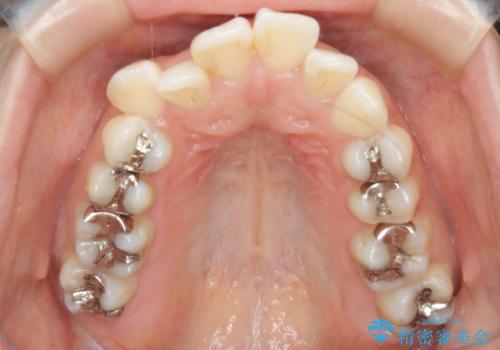

- 歯のガタつきと出っ歯が気になるので矯正治療を希望し来院された患者様です。

上下顎とも歯を並べられるスペースが無く、口元を下げたいというご希望だったので、抜歯とワイヤー矯正を併用した治療を計画しました。

抜歯スペースを利用し口元を大きく下げることが出来ました。